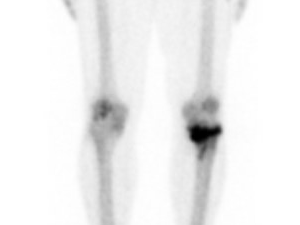

L’imagerie vient renforcer le diagnostic : la scintigraphie osseuse montre classiquement une hyperfixation dans la phase osseuse, tandis que l’IRM peut révéler un œdème médullaire, une déminéralisation mouchetée et des signes inflammatoires périarticulaires. Ces examens permettent de confirmer le diagnostic en cas de doute clinique ou d’évolution atypique.